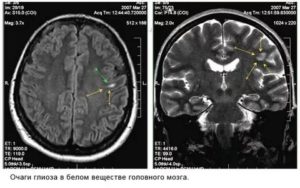

Справочно. Лучше всего визуализируются очаги глиоза на МРТ либо КТ-аппаратах.

Эти современные приборы позволяют с высокой точностью выявить сосудистые изменения, опухолевые процессы, патологические участки в белом веществе лобных долей, очаги кровоизлияний, ишемическое поражение.

Диагностика глиоза головного мозга основывается на данных КТ и МРТ:

- Магнитно-резонансная томография, является приоритетным методом для выявления таких отклонений. Помощью этого метода, специалист увидит очаги глиоза в мозге, выяснит степень распространенности и определит точную причину возникновения болезни.

- В случае глиоза, обычно в заключении МРТ может быть написано – «картина очага глиоза в левой (правой) лобной доли».

- Если очаги множественные, то данная методика выявит все места их локализации и масштабы гибели нейронов.

- Также магнитно-резонансный томограф определит причину возникновения таких очагов.

- Если виновником отмирания нервных клеток стало заболевание сосудистого характера, то в заключении МРТ будет написано – «картина единичного (множественных) очагов глиоза в белом веществе головного мозга – вероятно, сосудистого генеза». Подробнее о сосудистом генезе головного мозга и что это такое читайте в нашей аналогичной статье.